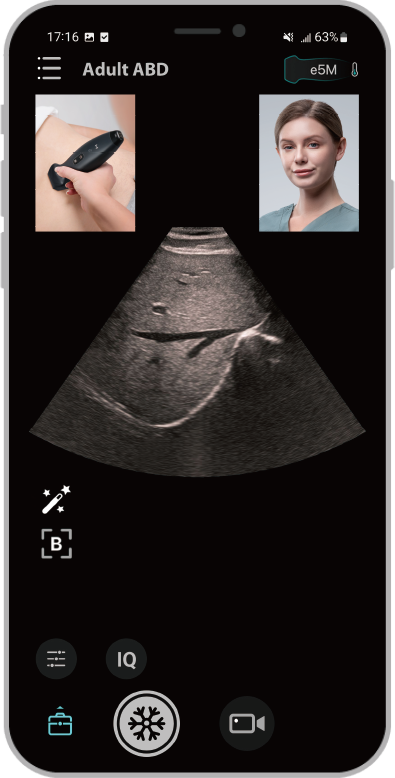

1Facile da usare, con un'interfaccia utente intuitiva

2Migliora l'efficienza grazie alla possibilitĂ di utilizzo con una sola mano